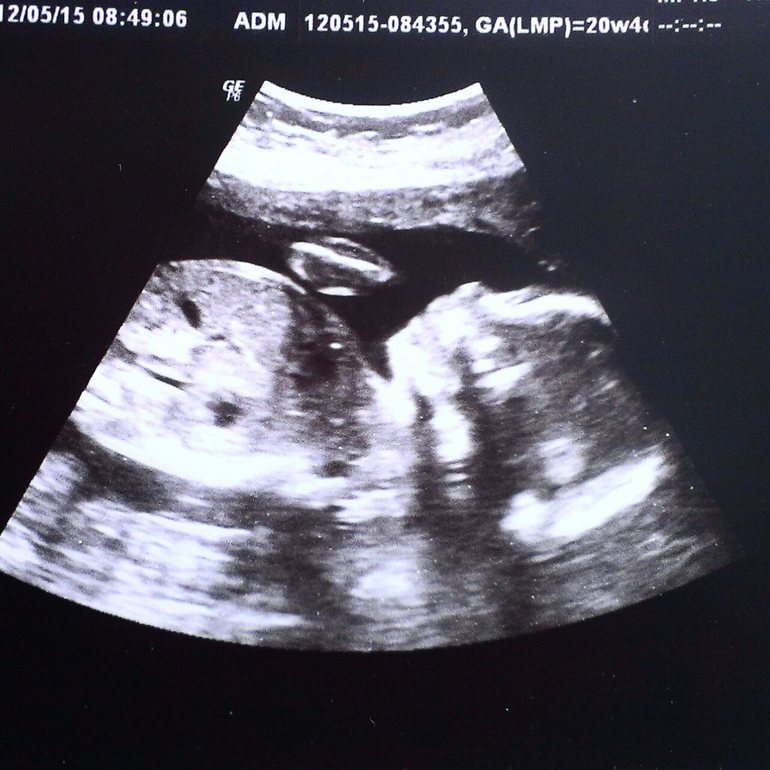

В заключение фото малыша)![]()

Узист молча измерил все параметры, потом медсестре назвал просто цифры в определенном порядке. Мне сказал только то, что мальчик без патологий. И на том спасибо!

Повернул монитор, чтобы показать фото, которое получилось. За фото 100 р - все, я свободна.